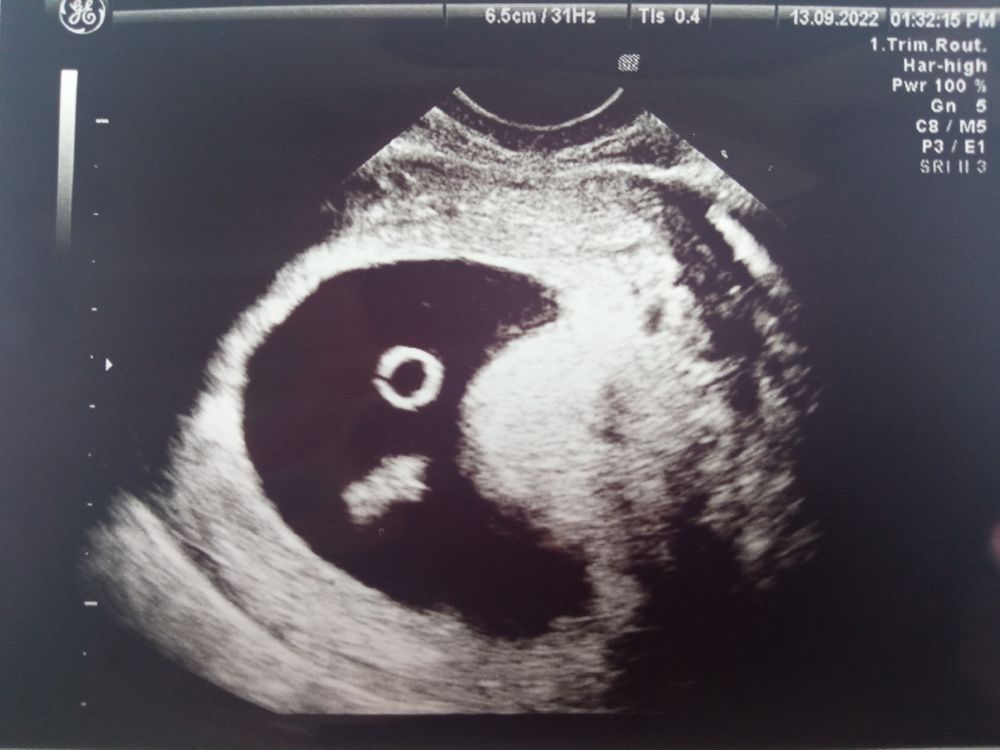

Изображение Акушерских 6+3, по КТР 7+4